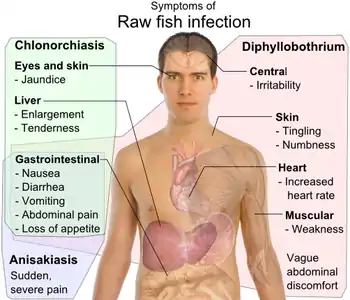

| Differential symptoms of parasite infection by raw fish: Clonorchis sinensis (trematode/fluke), Anisakis (nematode/roundworm) and Diphyllobothrium (cestode/tapeworm),[7] all have gastrointestinal, but otherwise distinct, symptoms.[8][9][10][11] | |

Anisakiasis is a human parasitic infection of the gastrointestinal tract caused by the consumption of raw or undercooked seafood containing larvae of the nematode Anisakis simplex.

Within a few hours of ingestion, the parasitic worm tries to burrow though the intestinal wall, but since it cannot penetrate it, it gets stuck and dies. The presence of the parasite triggers an immune response; immune cells surround the worms, forming a ball-like structure that can block the digestive system, causing severe abdominal pain, malnutrition, and vomiting. Occasionally, the larvae are regurgitated. If the larvae pass into the bowel or large intestine, a severe eosinophilic granulomatous response may also occur one to two weeks following infection, causing symptoms mimicking Crohn's disease.[12][13]

Acute allergic manifestations, such as urticaria and anaphylaxis, may occur with or without accompanying gastrointestinal symptoms. The frequency of allergic symptoms in connection with fish ingestion has led to the concept of gastroallergic anisakiasis, an acute IgE-mediated generalized reaction.[14] Occupational allergy, including asthma, conjunctivitis, and contact dermatitis, has been observed in fish processing workers.[24] Sensitivization and allergy are determined by skin-prick test and detection of specific antibodies against Anisakis. Hypersensitivity is indicated by a rapid rise in levels of IgE in the first several days following consumption of infected fish.[14] A 2018 review of cases in France has shown that allergic cases were more commonly found, although the number of human Anisakis infections was decreasing.[25]